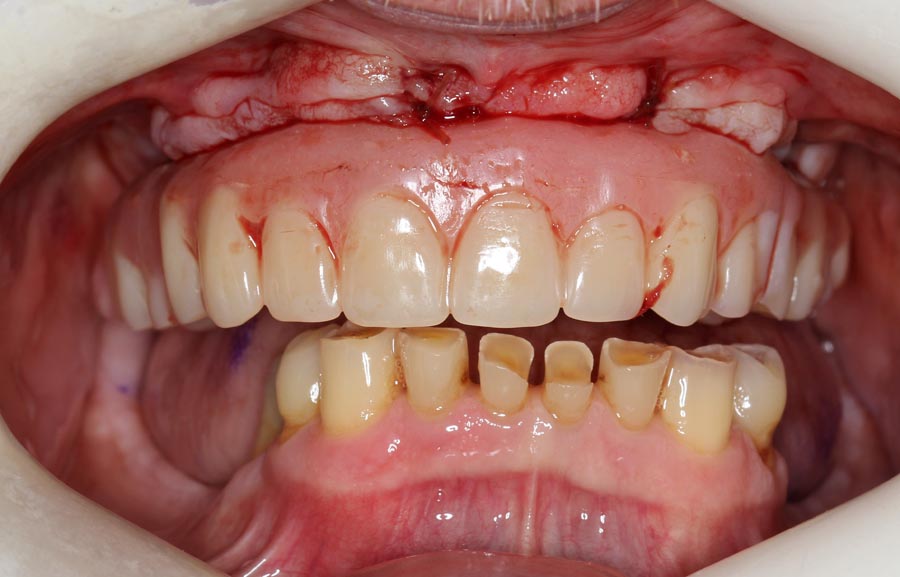

Frontal view of upper implant bridge (intra-oral). Just because the patient is delaying treatment on the lower doesn’t mean we can’t improve it for the year he is waiting. See next picture.

The lower teeth were bonded with composite resin to improve aesthetics and function during the year he is waiting to do his lower.